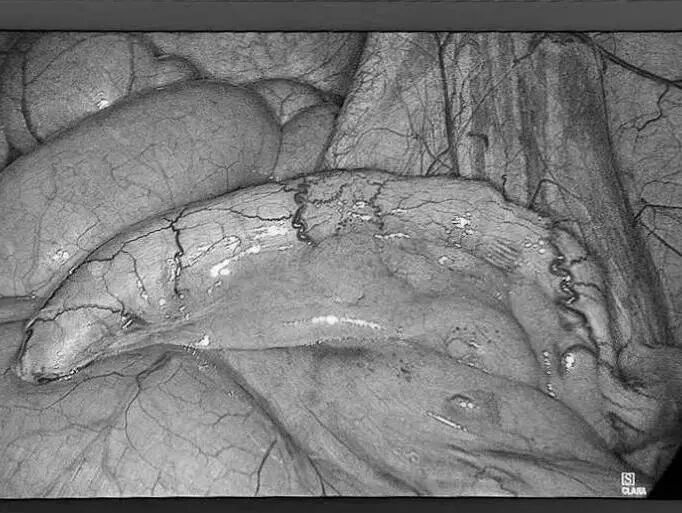

无数次立下减肥的誓言 尝试过五花八门的减肥方法 节食饿得头晕眼花 运动累得精疲力竭 但体重却像坐过山车 稍有松懈 就迅速反弹 别担心 或许减重手术 就是改变您体重的 关键契机 当前,肥胖已不仅仅是关乎外貌美观的问题,更像是一颗隐藏在身体里的定时炸弹,悄然引发各种慢性疾病。对于重度肥胖朋友来说,传统的饮食控制和运动往往收效甚微。而减重手术,为肥胖人群重获健康与自信带来了新的选择。 什么是减重手术? 减重手术,也被称为代谢手术,主要是对消化系统进行 “重塑”。目前,常见的手术方式有腹腔镜袖状胃切除术、腹腔镜胃旁路术及胃束带手术等。 比如,通过缩小胃容量,让您进食少量食物就有饱腹感,或者改变消化道结构,减少身体对营养的过度吸收。 胃旁路手术 袖状胃切除术 胃束带手术 减重手术真的有效果吗? 减重明显,告别肥胖 接受减重手术后,一般1到2年内,可以减掉超重体重的 60%-80%,让您告别肥胖困扰。 改善代谢,减少疾病 能够有效缓解Ⅱ型糖尿病、高血压、高血脂等肥胖相关疾病,让您重新拥有健康的身体状态。 减重手术,适合哪些人? 减重手术并非人人适用,需要经过严格、专业的术前评估。一般来讲,如果体重指数(BMI)≥30kg/m²,或者 体重指数(BMI)≥25 kg/m² 且合并有严重代谢性疾病,那么就可以将减重手术纳入考虑范围。 普外科专家简介 梁 跃 中共党员,普外科党支部书记、主任,主任医师 临床擅长:对普外科各类肿瘤手术具有丰富的临床经验。 毕业于遵义医学院,遵义市医学会小儿外科学分会常务委员,遵义市肛肠协会理事,遵义市医学会核医学分会(第二届)委员会委员;荣获第三期“黔医人才计划”优秀学员称号;主持市级课题1项,完成省级课题1项,在国内各类刊物上发表论文10余篇。 钱科洪 普外科副主任医师 临床擅长:从事普外科临床工作30余年,对各类普外科疾病的诊治、乳腺、甲状腺、胃十二指肠、结直肠等疾病及疑难杂症具有丰富的临床诊疗经验。 毕业于遵义医学院临床医疗系,2009年前往中山大学附属第一医院微创外科进修学习,在国内各专业期刊发表论文数篇。 贵州航天医院普外科简介 基本情况 贵州航天医院普外科成立于19世纪60年代,前身属于原航天部O61基地3417医院外一科,1998年更名为普外科,下设胃肠外科、肛肠外科2个亚专业科室,拥有专科设备和技术,是中国疝病专科联盟单位,贵州医科大学附属医院胃肠外科专科联盟单位。开放床位40张,配备医护人员21人。 专科特色 普外科致力于胃肠及肛肠疾病的外科临床诊治及科研,以腹腔镜微创外科技术为本,形成以快速康复治疗胃肿瘤、结直肠肿瘤、小肠肿瘤、直肠脱垂、肥胖病、急腹症、各类疝、痔、瘘等专科特色,同时注重胃肠疾病尤其是结直肠恶性肿瘤的基础研究和临床转化研究。 开展手术:腹腔镜下胃癌根治术,腹腔镜下袖状胃切除术,腹腔镜下胃肠道间质瘤切除术,腹腔镜下结、直肠癌根治术,胃癌、结直肠癌的精准治疗,腹腔镜下小儿疝气、成人疝修补术,腹腔镜下阑尾手术,内痔的硬化注射治疗及痔疮的微创治疗:ATH、PPH、TST,直肠脱垂的各种手术治疗,难治性伤口VSD技术,鼻胃肠管、肠梗阻导管置入术,肛肠术后间歇性导尿技术,并引进了中医适宜技术,也为各种化疗患者提供输液港安装,提高患者就医体验。 腹腔镜下腹股沟疝无张力修补术 腹腔镜下腹股沟疝 无张力修补术 腹股沟疝里金斯坦(Lichtenstein)手术 PPH微创术治疗环状混合痔 黏连性或炎性肠梗阻-肠梗阻导管 腹腔镜袖状胃切除 腹腔镜阑尾 切除术 腹腔镜阑尾肿瘤 切除术 腹腔镜下结肠癌根治术 诊疗范围 胃肿瘤、结直肠肿瘤、小肠肿瘤、肥胖症、各类急腹症、腹部外伤、腹壁疝、便秘、直肠脱垂、痔疮、肛瘘、肛裂等胃肠、肛肠外科疾病。 END